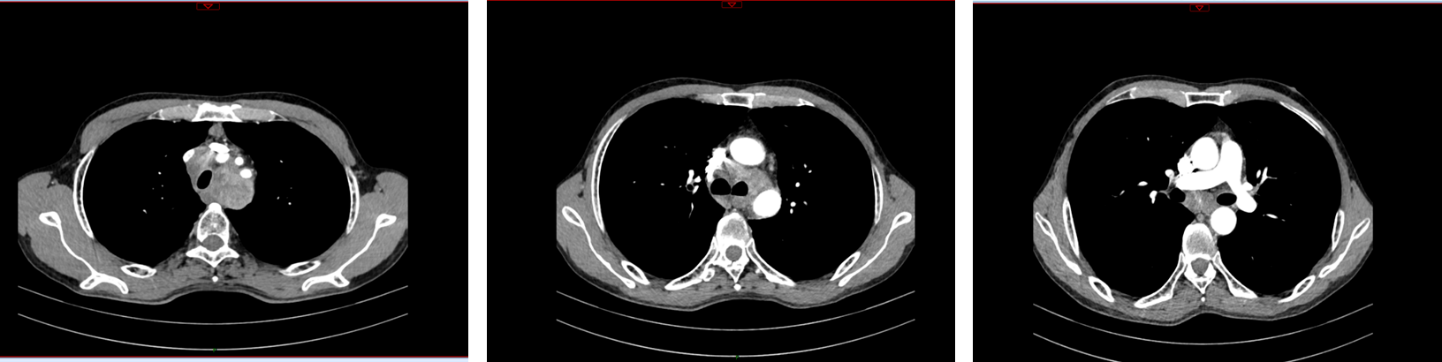

图1 胸部CT(2018年8月7日)

2018年8月7日因进食梗阻感复查CT示:纵隔内淋巴结明显增多增大,较大者截面径约4.0cm×3.3cm,考虑转移。再次分期rⅣ期(纵隔淋巴结转移)。2018年8月—11月行一线GP方案4周期。2018年11月26日予以纵隔转移灶放疗50Gy/25F,期间同步顺铂化疗4次,每次40mg/㎡,因患者治疗期间出现Ⅳ度血小板减少、Ⅱ度白细胞减少,放疗完成23次。治疗后疗效评价PR。患者回当地医院行营养支持及对症治疗。